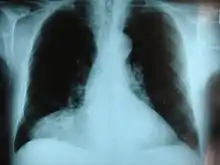

Hernie diaphragmatique congénitale

- une hernie diaphragmatique,